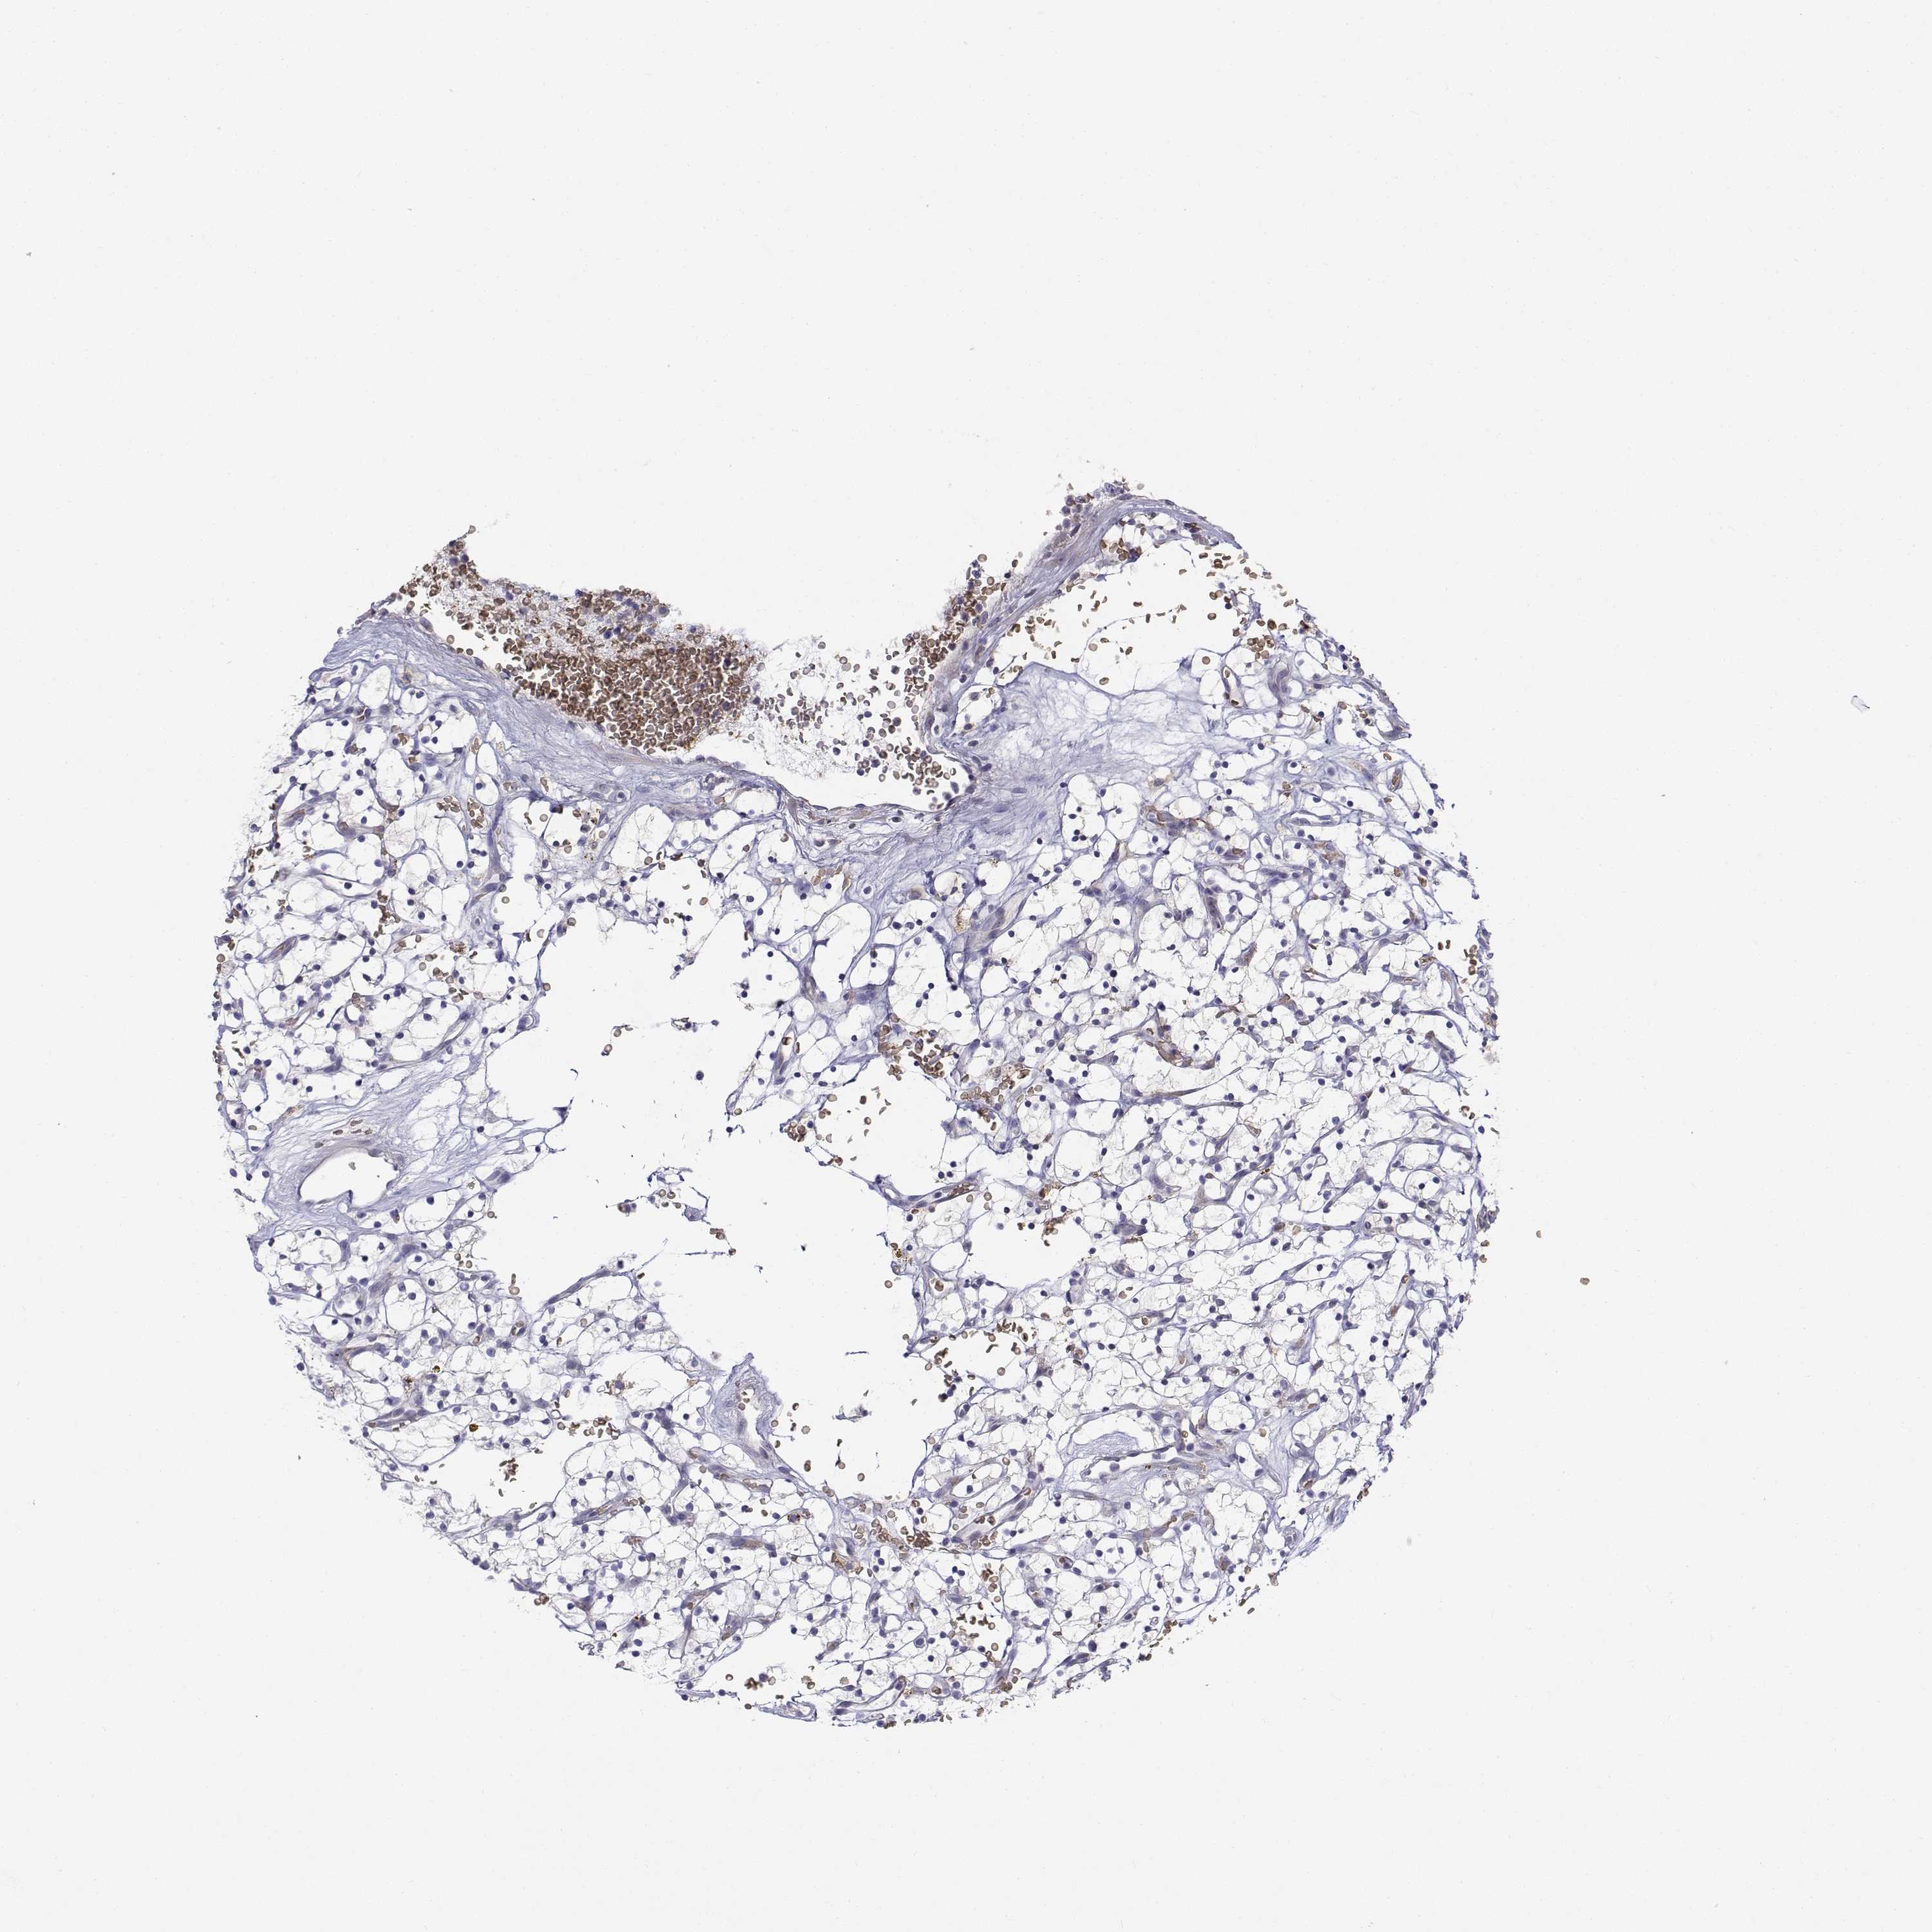

CADM1

CANCER RENAL CANCER Show tissue menu

KICH TCGA KIRC TCGA KIRC VALIDATION KIRP TCGA PROTEIN RCC CPTAC PROTEIN EXPRESSION